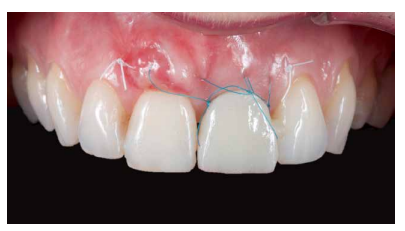

Debido a la presencia de una recesión gingival de 2 mm en el ICSD, el ITC que se obtuvo fue del tamaño suficiente para abarcar la región de este diente y poder tratar dicha recesión de forma simultánea al procedimiento sobre el IOI. Se adaptó a la región receptora con sutura 5.0 de politetrafluiretileno (PTFE) con puntos de fijación en mesial y distal, lo que garantizaba la correcta vascularización del injerto (Figuras 14A, 14B, 14C).

del mismo de forma tunelizada. 14B. Detalle del injerto de tejido conectivo de origen palatino. Se puede observar la longitud del mismo que comprende tanto el alveolo del diente 2.1 así como el diente 1.1 con el fin de mejorar el biotipo gingival y disminuir la recesión gingival presente en el diente 1.1. 14C. Injerto de tejido conectivo tunelizado y fijado mediante sutura PTFE en mesial y distal. Se puede observar el volumen

perioperatorio del tejido blando.